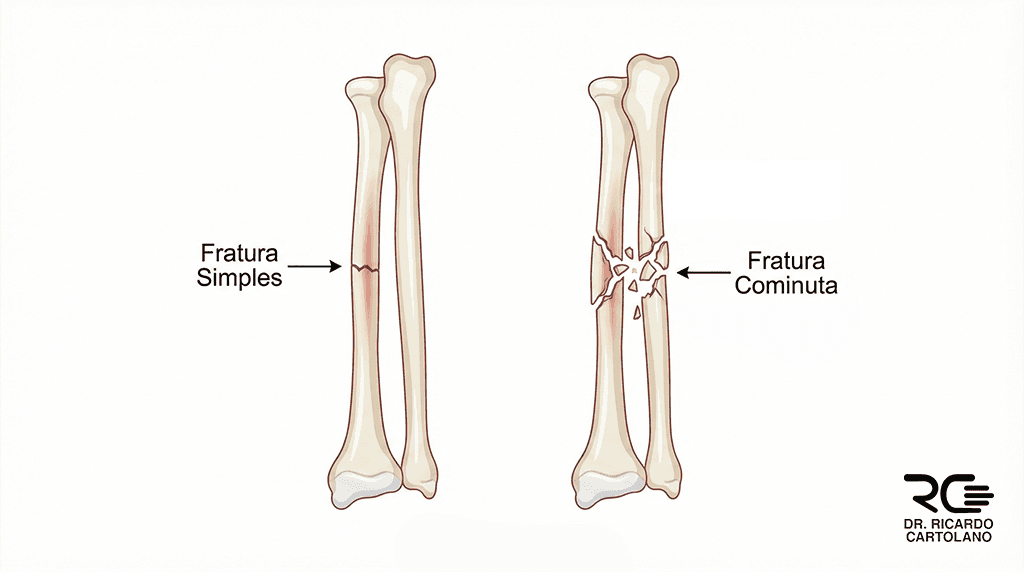

Classificação pelo Traço (Geometria)

Fratura Simples: Ocorre quando há apenas um traço de fratura, dividindo o osso em duas partes. Geralmente, é mais fácil de alinhar e tratar.

Fratura Cominuta: Uma lesão de alta energia onde o osso se fragmenta em três ou mais pedaços. É como um ‘quebra-cabeça’ que exige reconstrução cirúrgica complexa e placas especiais para estabilização.